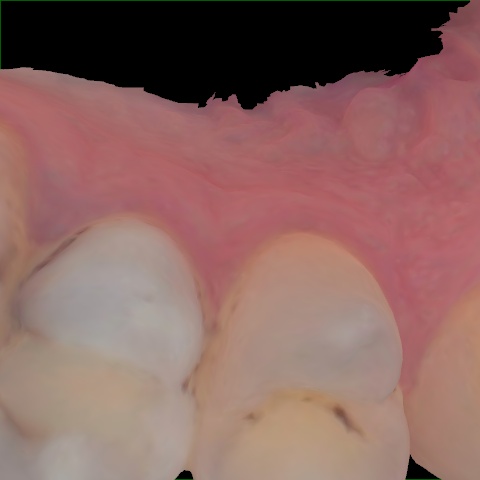

Image 1618 / 2000

NHD39969

Annotated as "Good"

Original Image Rendering Image